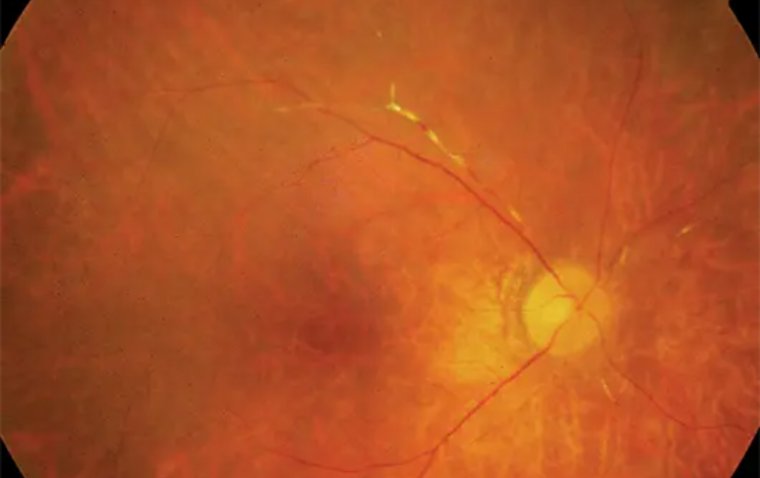

Ретинальный васкулит: причины возникновения, клиническая картина и подходы к терапии

Ретинальный васкулит — воспалительное заболевание сосудов сетчатки, которое может приводить к затуманиванию зрения, фотопсии, плавающим помутнениям и потере периферического поля зрения. В статье рассмотрены причины (аутоиммунные, инфекционные, лекарственные), механизмы развития, …